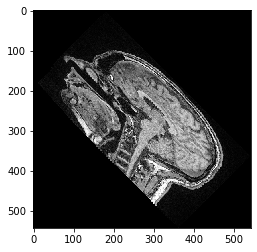

scale_factor = 2

transform = cle.AffineTransform3D()

transform.scale(scale_x=scale_factor)

cle_translated2 = cle.affine_transform(image, transform=transform, auto_size=True)

cle.imshow(cle_translated2[100])